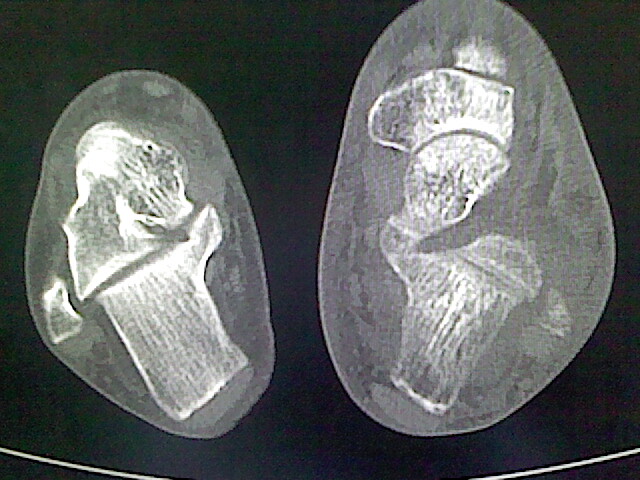

标题: CT16814:男,76岁,左小腿疼痛,不能站立 大家给看看 [打印本页]

男,76岁,左小腿疼痛,不能站立

本例骨质改变主要表现为滑膜或韧带区的骨侵蚀融解(胫腓联合区骨质破坏无硬化边),距骨后部骨质破坏区有硬化边及死骨样改变.所以,本例考虑关节结核可能性大,绒毛膜结节性滑膜炎多发于中年,且极少见于膝髋以外的关节,骨质硬坏也以压陷吸收为主,有明显的硬化边,骨膜增生呈结节状(可以mr鉴别),所以本例暂除外.

另不除外可引起相似表现的其他炎症如布氏杆菌性关节炎等